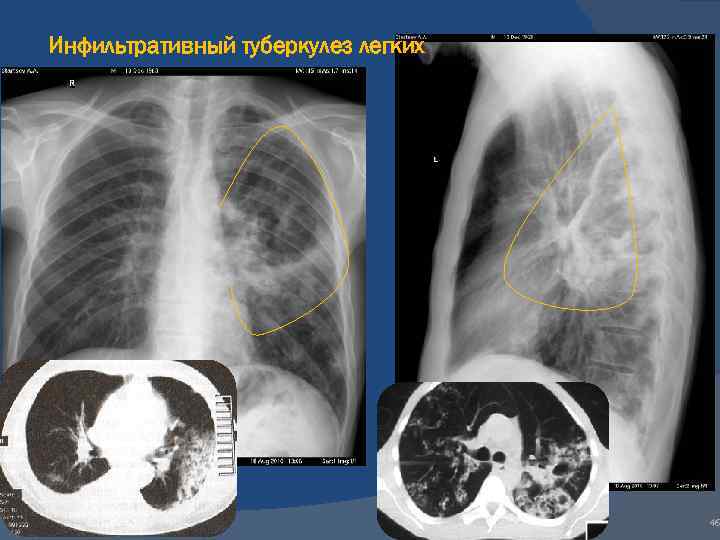

Симптомы и лечение инфильтративного туберкулеза легких

Раздел: Снимки-откровения